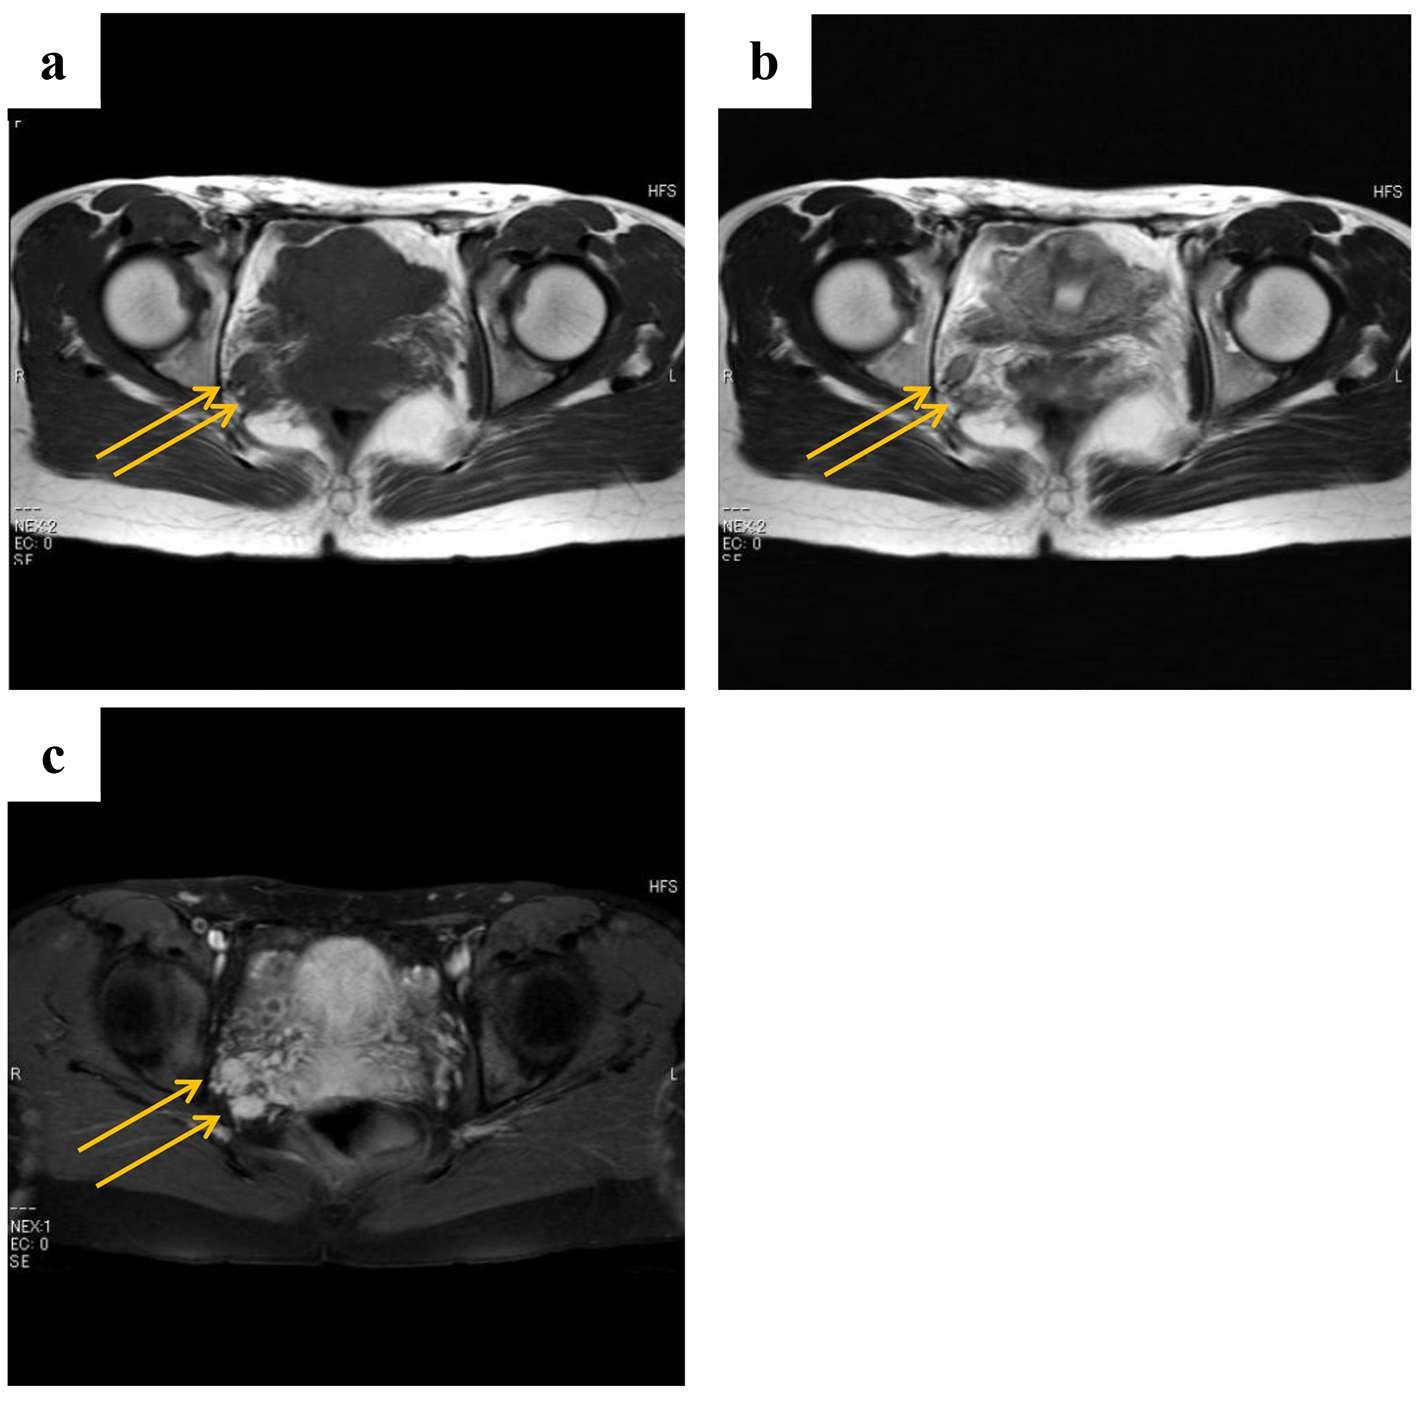

Figure 3. Magnetic resonance images obtained at 2 years and 3 months after surgery (a: T1-weighted images; b: T2-weighted images; c: gadolinium contrast). The patient had tumor recurrence that was evident as two enhanced masses (1 cm in diameter) located a little behind the preoperative point, namely the right internal obturator muscle.